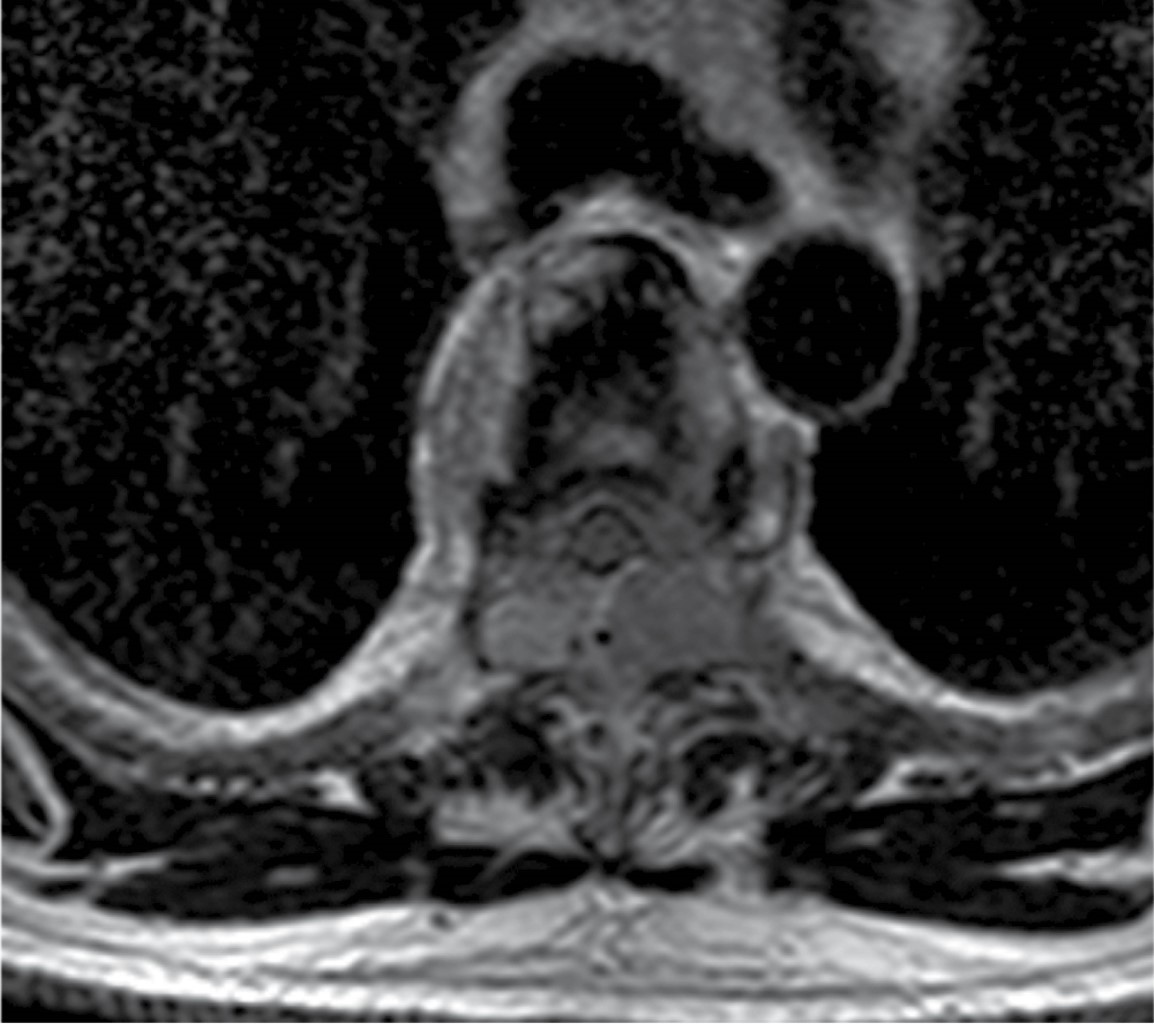

A la exploración neurológica con fuerza 1/5 en miembros inferiores se observa hipotonía, reflejos de estiramiento muscular de miembros inferiores 1/4, con hipoestesia por debajo de T4. Se realizó resonancia magnética en vista sagital secuencia T2, donde se aprecia lesión hipointensa epidural localizada en T4-T5 de bordes regulares con dimensiones de 35 × 6 mm que, de acuerdo con la clasificación de SINS, obtuvo puntaje de 4, catalogándose como columna inestable. Por lo anterior se decidió realizar cirugía, la cual consistió en hemilaminectomía de T4-T5 más exéresis tumoral, reportándose en el examen de patología transquirúrgico como plasmocitoma (Figuras 1, 2 y 3).

Durante el postquirúrgico mediato el paciente presentó mejoría de la fuerza de miembros inferiores 4/5. Se realizó protocolo de estudio para MM por parte del servicio de medicina interna, en donde se encontró, en aspiración de médula ósea, células clonales plasmáticas mayores al 10%, hipercalcemia de 13 mg/dl, creatinina de 2 g/dl. En la resonancia magnética de control se observó adecuada resección tumoral.

A diferencia de lo que proponen algunos algoritmos de manejo conservador inicial sólo con radioterapia, en este caso se optó por intervención quirúrgica temprana con biopsia escisional como estrategia diagnóstica y terapéutica simultánea. Esta decisión, fundamentada en la presencia de déficit neurológico progresivo y compresión medular evidente en la resonancia magnética, permitió una descompresión efectiva y un rápido control local de la enfermedad.